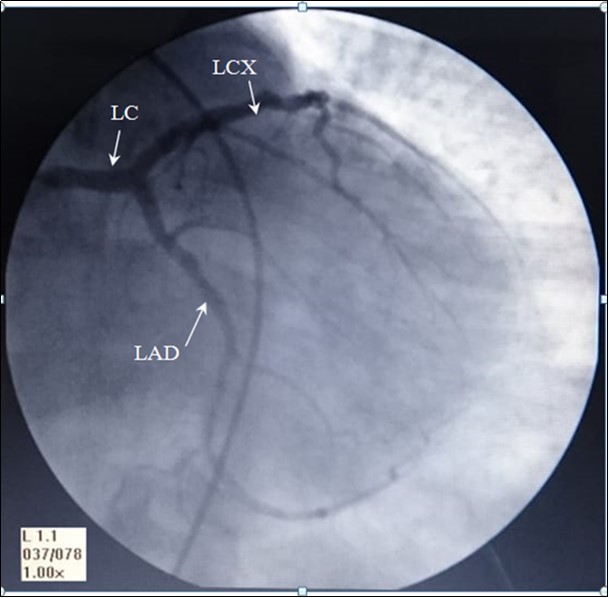

The angiography of these arteries is illustrated in Figure 1.

Figure 1.AP- anteroposterior angiographic view showing, Left coronary artery: LC, left anterior interventricular ( anterior descending) artery: LAD, and Left Circumflex artery: LCX

The angiographic measurement of the left coronary (LC) diameter was found in the range between 2.90- 4.90mm, mean 3.96, and Std. Dev. 0.549mm. The left circumflex artery's diameter was found in the range between1.70- 4.70mm, mean 2.73 and Std. Deviation .687mm. The diameter of the anterior interventricular artery was found in the range between 1.20- 4.70mm, mean 2.78, and Std. Deviation .825mm. these diameters are blotted in the Graph 1.